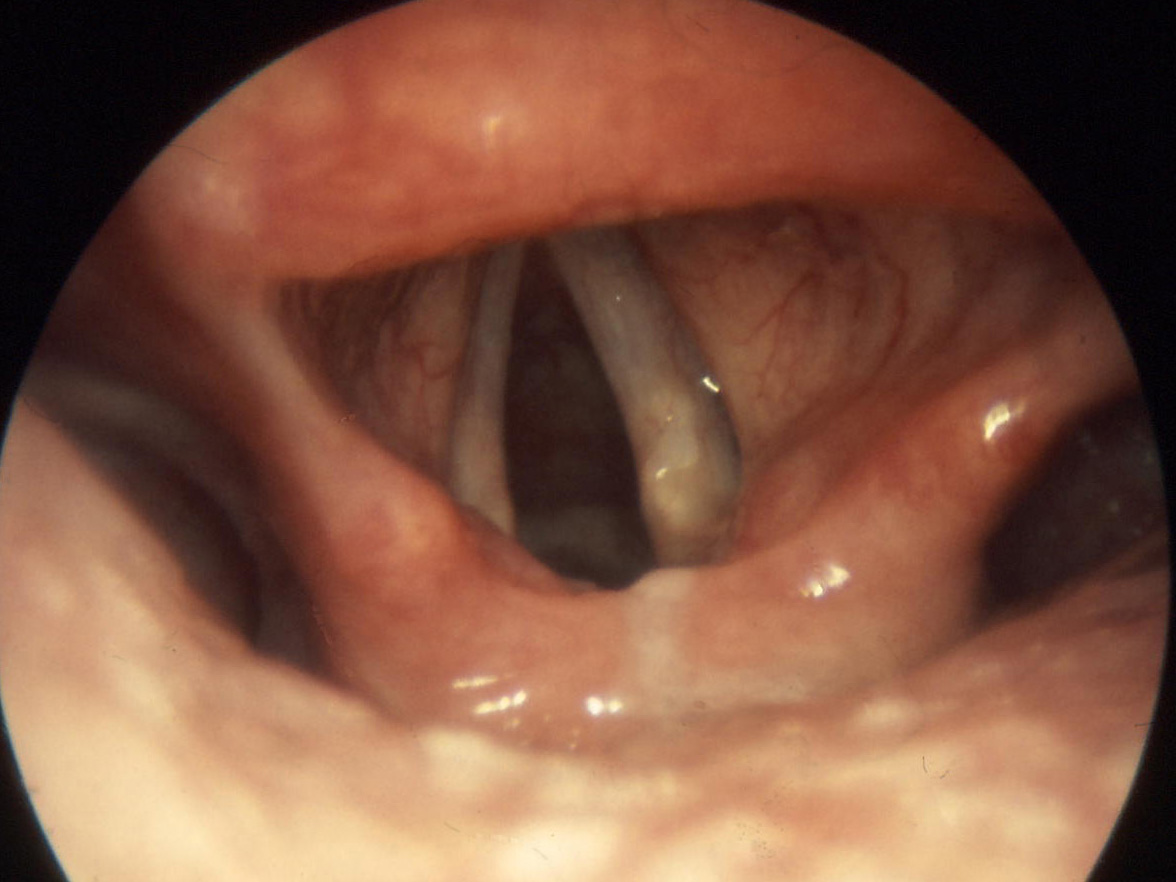

Per tonsillite acuta si intende comunemente l’infiammazione delle tonsille palatine, visibili nell’orofaringe, lateralmente all’ugola. A partire dalla prima infanzia, le tonsille palatine vanno incontro a una progressiva atrofia.

Le tonsille sono esposte a infiammazione, più spesso dovute a virus e, più raramente, a batteri, che ne causano un ingrandimento, accompagnato da sintomatologia dolorosa.